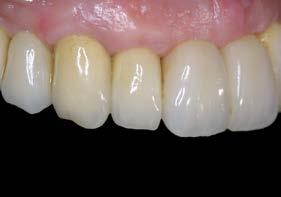

Una vez finalizados los postes, se prueban antes del cementado de las coronas para verificar que la zona ceramizada genere un margen gingival estético, evitando la exposición de metal incluso ante una posible recesión gingival leve. Asimismo, el hombro de la restauración se sitúa a nivel yuxtagingival, con el fin de evitar la presencia de cemento subgingival durante el cementado. Posteriormente se realiza la prueba de coronas (Figura 9) y su colocación definitiva (Figuras 10–12).

En una visión ampliada de la zona anterosuperior se aprecia la adecuada adaptación de los tejidos blandos a las coronas, lograda mediante la provisionalización y el diseño de pónticos y pilares que favorecen un contorno gingival armónico (Figuras 13 y 15).

La paciente continúa bajo seguimiento periodontal. A los 5 años se observa estabilidad clínica del tratamiento (Figuras 22–24), sin recesiones gingivales ni pérdida ósea asociada en las imágenes clínicas y radiográficas.

Un año más tarde, al finalizar el periodo de seguimiento (24 años), las fotografías intraorales evidenciaron ligeras alteraciones de los tejidos blandos, con pequeñas troneras abiertas,

más evidentes en los dientes naturales conservados que en las restauraciones implantosoportadas. A pesar de estos cambios, el resultado global se consideró satisfactorio desde el punto de vista funcional y estético, especialmente en comparación con la situación clínica y radiográfica inicial previa al tratamiento (Figuras 26–31).